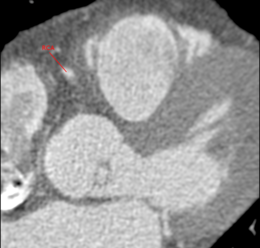

Medical imaging is used for the diagnosis of CAD and for the quantification and grading of stenosis. The extraction of the central lumen line (centerline) of coronary arteries is helpful for visualization purposes, stenosis quantification or further processing steps (e.g. reformatting) [Schaap2009]. This tutorial shows how to use tools based on the Vascular Modeling Toolkit (VMTK) ([Antiga2008]) in 3D Slicer to segment the right coronary artery (A. coronaria dextra, RCA) in a computed tomography angiography (CTA) volume and extract the associated centerline. In particular the segmentation is performed on a CTA dataset which was obtained through the Rotterdam Coronary Artery Algorithm Evaluation Framework ([Schaap2009]). Even if this documentation shows how to establish a work flow between three VMTK in 3D Slicer tools, each of the three documented segmentation steps can be considered as a guide for the individual module.

Due to time-consuming calculations, it is highly recommended to extract a subvolume of the region of interest prior to the segmentation process. This can be done by using Converters -> Extract Subvolume or Converters -> Extract Subvolume ROI in the 3D Slicer module selector.